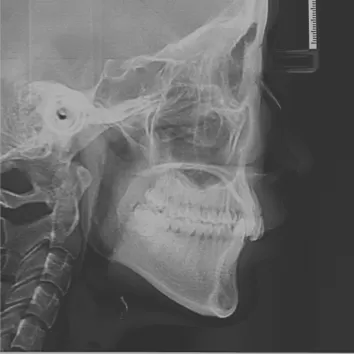

X-rays before treatment

[Panoramic Radiography/Lateral Cephalogram]